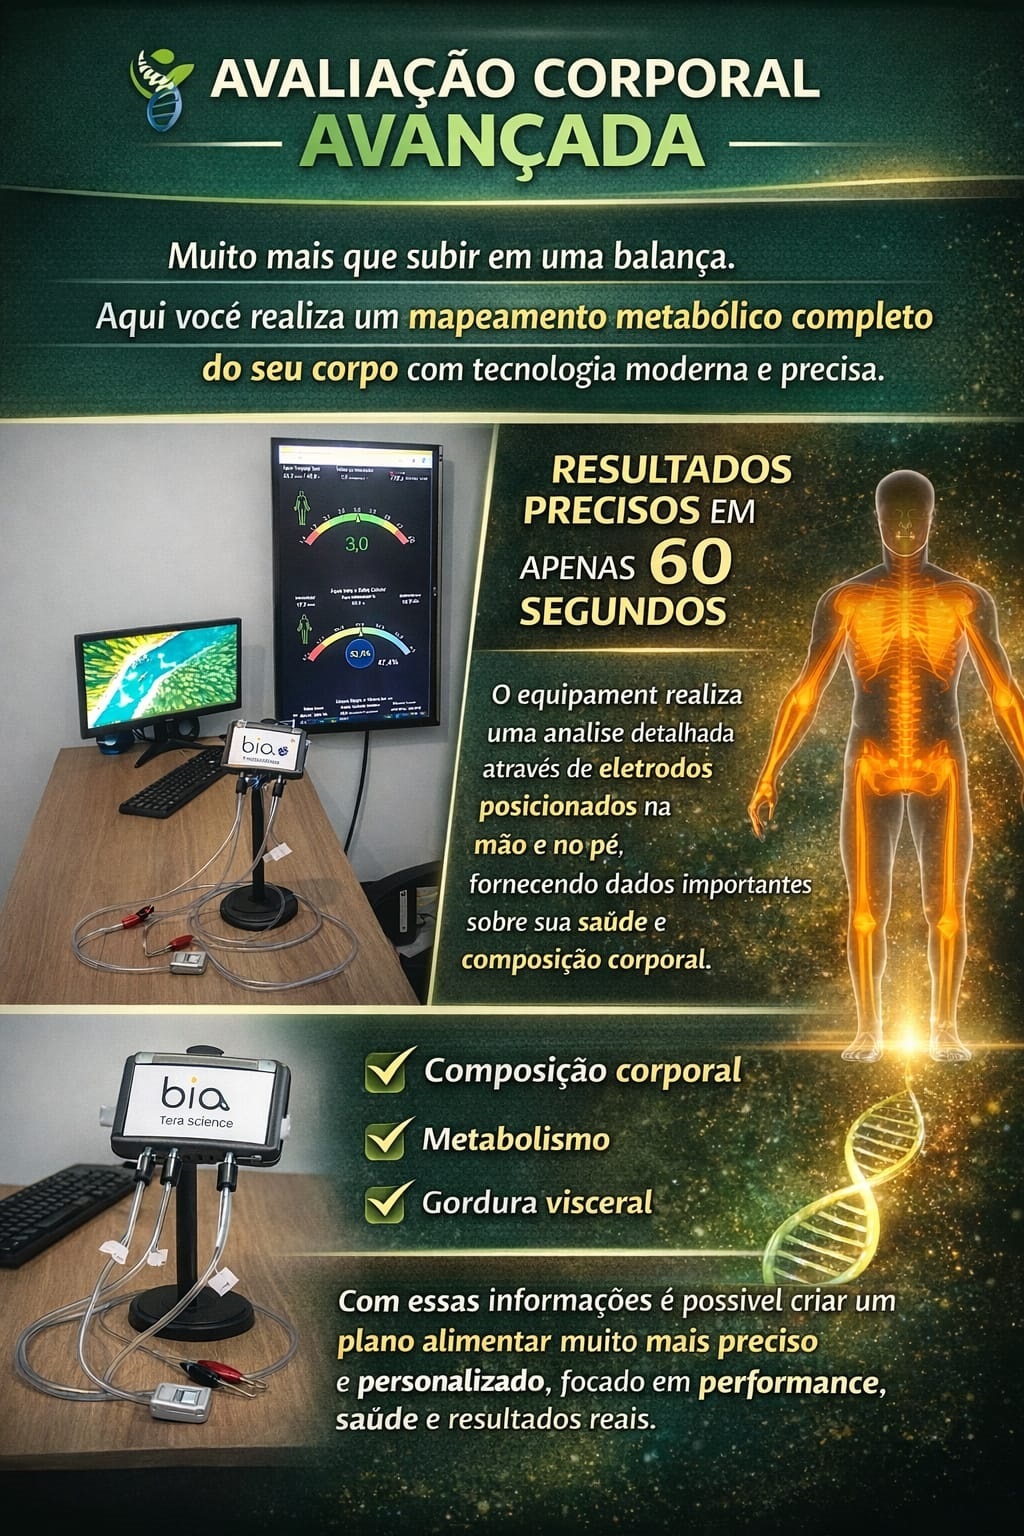

Muito além de uma simples balança!

Com tecnologia tetrapolar multifrequencial, oferecemos um método moderno e altamente preciso de análise corporal.

Em apenas 60 segundos, quatro eletrodos posicionados na mão e no pé direitos realizam um mapeamento metabólico completo, fornecendo informações detalhadas sobre o funcionamento do seu corpo.

Biomarcadores avaliados:

Análise metabólica aprofundada

Composição corporal: gordura e massa muscular

Ângulo de Fase: indicador essencial da vitalidade celular e de processos inflamatórios

Hidratação intra e extracelular

Gordura visceral

Esses dados permitem a elaboração de um plano alimentar personalizado e muito mais preciso, totalmente focado na sua saúde, bem-estar e resultados.